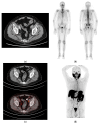

This prospective study aimed to (1) compare the diagnostic performance of 68Ga-PSMA-11 PET/CT with respect to conventional imaging (computed tomography (CT) and bone scintigraphy (BS)) in the primary staging of high-risk prostate cancer (PCa) patients and (2) validate PSMA-PET/CT accuracy in pelvic nodal staging in comparison with postoperative histopathology and assess PSMA-PET/CT's impact on patient management. Sixty castration-sensitive high-risk (ISUP 4-5 and/or PSA > 20 ng/mL and/or cT3) PCa patients eligible for radical prostatectomy were enrolled (median PSA 10.10 [IQR: 6.22-17.95] ng/mL). PSMA-PET/CT, compared with CT, identified nodal (N) and/or distant metastases (M1) in 56.7% (34/60) vs. 13.3% (8/60) (p < 0.001) of patients: N + 45% vs. 13.3% (p < 0.001), M1a 11.7% vs. 1.7% (p = 0.03), M1b 23.3% vs. 1.7% (p < 0.001). Compared with BS, PSMA-PET/CT localized unknown skeletal metastases in 15% (9/60) of cases, with no false negative findings. Overall, PSMA-PET/CT led to a TNM upstaging in 45.0% (27/60) of cases, with no evidence of downstaging, resulting in a change in management in up to 28.8% (17/59) of patients. Compared with histopathology data (n = 32 patients), the per-patient accuracy of PSMA-PET/TC for detecting pelvic nodal metastases was 90.6%. Overall, the above evidence supports the use of PSMA-PET/CT in the diagnostic workup of high-risk prostate cancer staging.